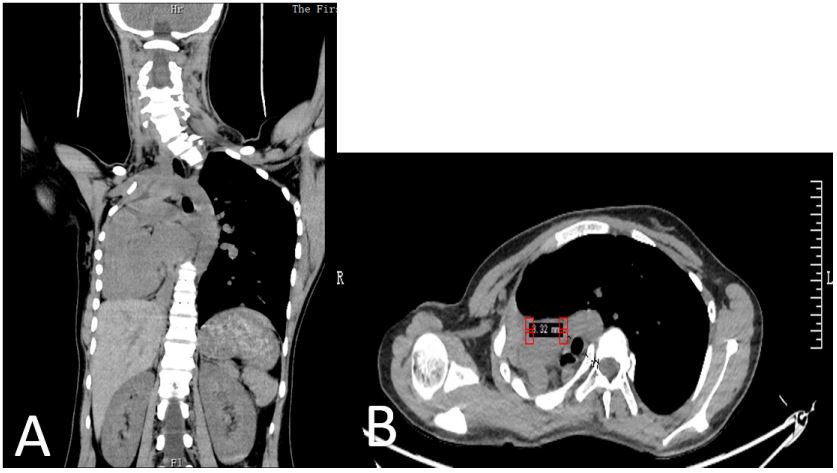

A 15-year-old female came to our hospital complaining of shoulder imbalance, where the right side is higher than the left. She was diagnosed with scoliosis four years ago, and no sort of treatment was done. Her medical history was significant for congenital right lung agenesis with dextrocardia and left lung hyperinflation. She was symptomatic and could not tolerate normal daily physical activity. The severity of the spine curvature further exacerbated her pulmonary limitation, which led to her symptoms. Due to the patient’s concern over the appearance of her back and the long-term negative impact of signs and symptoms on her health, she was advised to undergo surgery. Considering all the risks related to the surgery and her medical history, the patient agreed to undergo the surgery, which was performed at the First Affiliated Hospital of Zhengzhou University. Before the surgery, due to her history of unilateral lung agenesis, she had to go through vast and thorough testing and laboratory investigations to determine if she could tolerate a major surgery. Physical examination revealed a tall, underweight girl with normal vital signs. Shortness of breath upon exertion with no other comorbidity or past surgical intervention. In addition, an electrocardiogram shows signs of tachycardia. Cardiac ultrasound revealed that the heart is on the right side with no signs of right lung parenchyma. Bronchoscopy showed that the larynx and vocal cords are normal, the trachea is twisted and deformed with no obstruction, and there is an abrupt ending of the right main bronchus at the Carina. The lung function test showed reduced total lung volume, reduced residual gas volume, reduced functional residual capacity, and decreased vital capacity. A chest X-ray performed at admission showed opacity on the right thorax, together with deviation of the trachea and mediastinum to the right. Scoliosis at the upper thoracic spine with a Cobb angle of 43.33 (Figure 1A). Chest computed tomography CT showed collapse of the right lung with respiratory dead spaces, compensatory hyperinflation, and herniation of the left lung to the opposite side. The heart and mediastinum are displaced so far to the right that they can easily be mistaken for situs inversus (FigURE 2A). After successful anesthesia, the surgical team proceeded with placing the patient on the prone side with adequate padding on both sides, leaving the abdomen hanging free. Next, a 25-cm skin incision is made from approximately the seventh cervical vertebra to the ninth thoracic. Then the underneath fascia is incised, the muscles are stripped until both facet joints are visible, and the laminae are fully exposed. With the help of a 3D-printed model of the patient’s spine, 17 trial screws left C7, left T2-T9 and right C7, right T2-T4, right T6-T9 were safely implanted, and correct placement was confirmed with fluoroscopy (Figure 1B). Instrumentation is then used to reduce the curvature of the spine. This involves placing permanent screws at each vertebral level mentioned above, and then a contoured rod is attached to these screws at each level and correction is performed. Left T1, right T1, and right T5 pedicles were particularly narrow, which made it difficult to place the screws (Figure 2B). Once the instrumentation was placed securely and a satisfactory correction was achieved, a final tightening was done. Lastly, the incision is washed, closed and dressed. Postoperatively, the patient was in good condition, with perfect vital signs and no pulmonary complications. Post-operative radiographs showed an improved Cobb angle of 17.8 degrees (Figure 1C), as well as marked improvement in her respiratory function, as evidenced by her ability to be extubated and resume activities of daily living. The patient was discharged 11 days after surgery and was advised to wear a thoracic-lumbo-sacral orthosis TLSO brace for 3 months and come for regular follow-ups.

Figure 2: CT (A) show complete absence of the right lung with Dextrocardia. (B) CT axial cut at T5 show narrow pedicle at the right side.